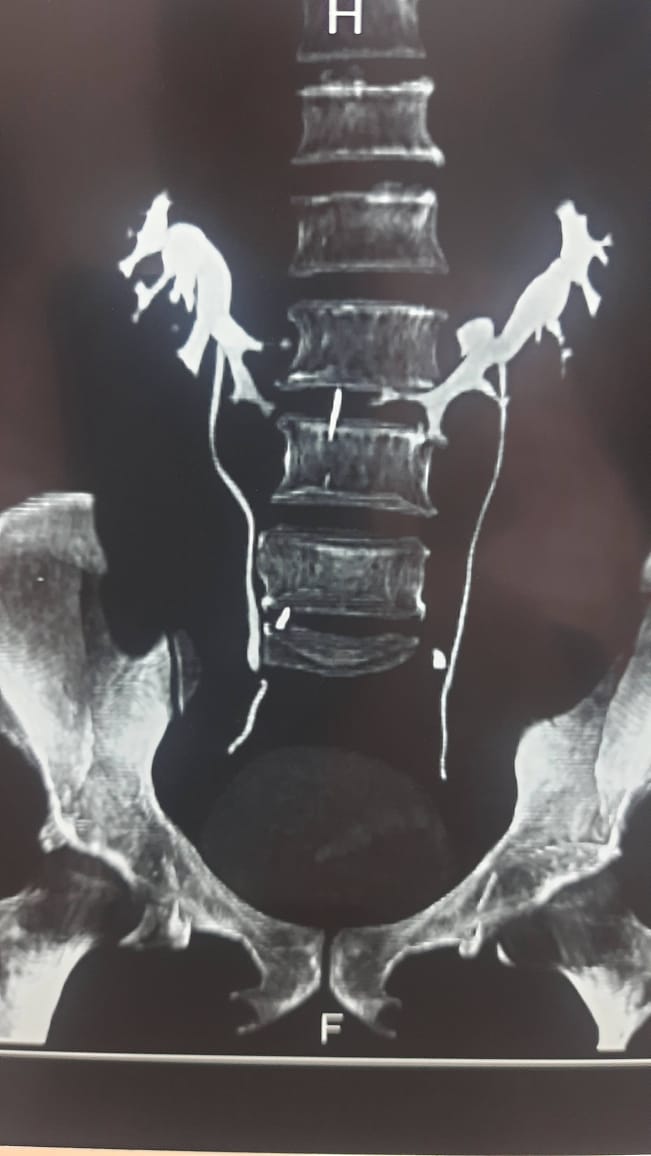

2. Clinical Work at Center